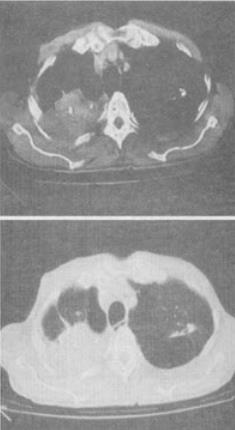

男,42岁,反复左侧腰部疼痛伴血尿3个月余,CT检查如图,下列说法错误的是()。

A:左侧输尿管内可见多发的高密度影

B:左侧输尿管上段扩张

C:左侧肾盂肾盏扩张

D:左输尿管结核并左肾积水

E:考虑为左输尿管结石并积水